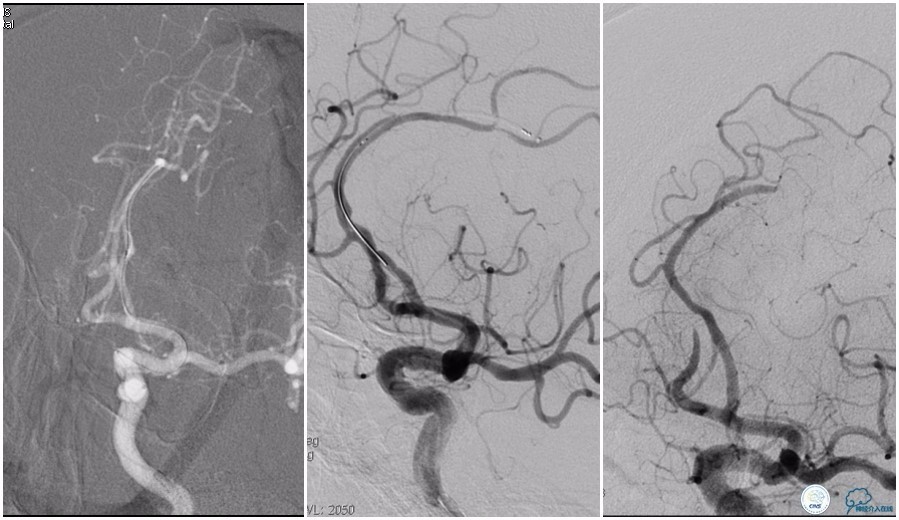

6F Envoy置于左侧颈内动脉C3段,选用Solitaire-FR 4*20mm支架释放于右侧大脑前动脉取栓1次,血流达TICI 2b。

Solitaire-FR 4*20mm支架释放于左侧大脑前动脉取栓1次,取出少许血栓重复造影左侧大脑前动脉胼周动脉开口后,右侧大脑前动脉A2段以远未显影,考虑栓子逃逸。

选用Solitaire-FR 4*20mm支架分别于右侧大脑前动脉A2-A3段,左侧胼周动脉,右侧胼周动脉取栓3次。